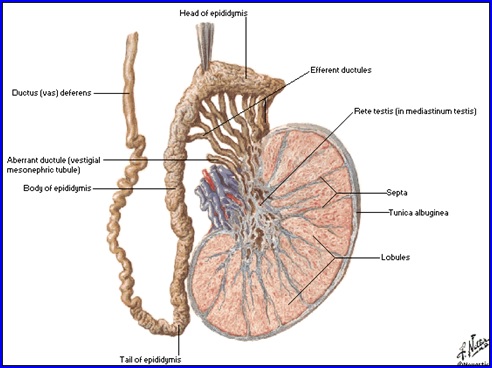

Testiculul

Dimensiuni: 4x3x2,5 cm, formă ovoidă, 20-25 g.

Structură:

- a exterior-albugineea: trimite septuri conjunctivo-vasculare în parenchim, delimitând 200-300 lobuli

- fiecare lobul conţine 1-4 tubi seminiferi ce converg în mediastinul testicular si se unesc cu canalele eferente

Vascularizaţie:

Arterială:

- a. testiculară (r. din aorta abd.)

- a. deferenţială (r. din a. vezicală inf.)

- a. spermatică ext. )r. din a. epigastrică inf.)

Venoasă:

- vv. testiculare şi epididimare ce se anastomozează formând plexul pampiniform dispus ant. şi post. de funicul® v.testiculară

Testicul, epididim si duct deferent: